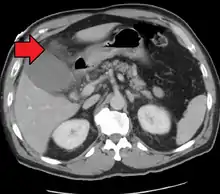

Right upper quadrant abdominal ultrasound is most commonly used to diagnose cholecystitis.[1][26][27] Ultrasound findings suggestive of acute cholecystitis include gallstones, pericholecystic fluid (fluid surrounding the gallbladder), gallbladder wall thickening (wall thickness over 3 mm),[28] dilation of the bile duct, and sonographic Murphy's sign.[13] Given its higher sensitivity, hepatic iminodiacetic acid (HIDA) scan can be used if ultrasound is not diagnostic.[13][14] CT scan may also be used if complications such as perforation or gangrene are suspected.[14]

Acute cholecystitis with gallbladder wall thickening, a large gallstone, and a large gallbladder- Significant gallbladder wall thickening[29]